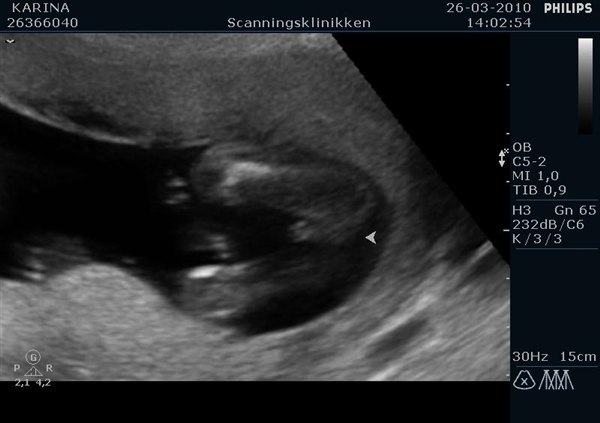

Vial

Det er jo rigtig svært at se for det utrænede øje.

Meeen i og med at der er samme køn og scanningsdamen mener, at begge kunne være drenge, så er det nok to små knægte.

Har I tænkt på navne endnu?

Du kan lige se mine babyers køn fra da de var 16+6. Havde jeg ikke vidst det, så kunne jeg da ikke se forskel...kan du?

Vedhæftede fotos (klik for at se i fuld størrelse)

den er ikke nem men drengen er nemmere at se end pigen må jeg sige. Men mine må jo være drenge så, men tøt ik helt tro det før vi har fået det tjekket igen på tirsdag hehe